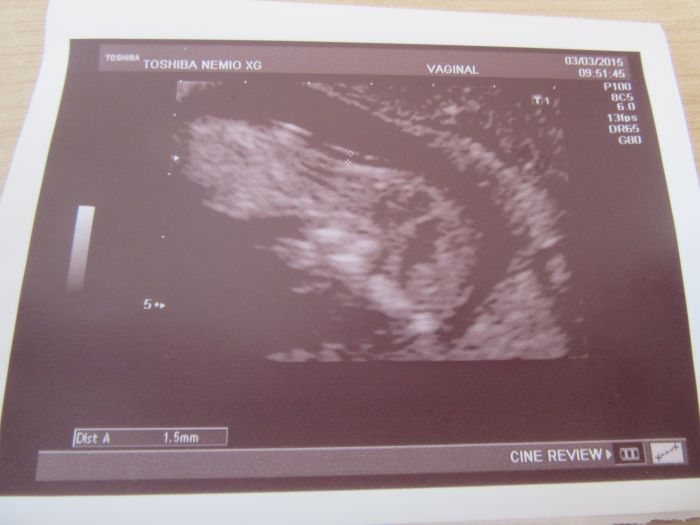

Ahoj holky, tak to dneska klaplo, jsem šťastná. Screening dopadl dobře, vše je v naprostém pořádku a za 14 dní se dozvím jak dopadla krev, pokud se jim něco nebude líbit tak se ozvou. Jinak mně vše ukázal i jak mám plný nacpaný žaludeček, to jsem teda koukala, nebude to zatím žádný divoch,jen trošičku se tam hýbal, ale moc tomu nedal. Jsem dnes 12+1 a měříme 5,53cm. Přikládám fotečky.